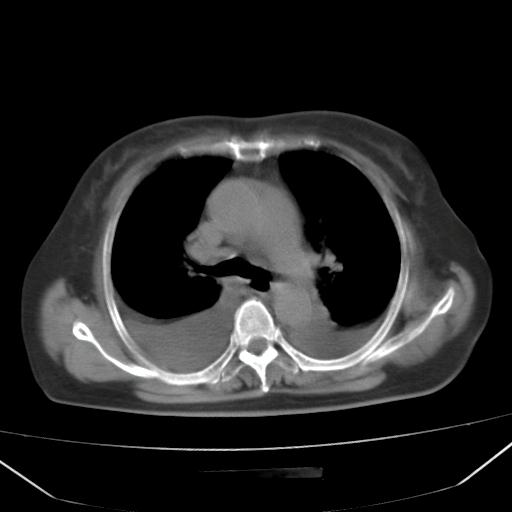

以下是引用liuyue在2008-4-19 22:25:00的发言:[br]先考虑:1.心衰伴肺水肿、双侧胸腔积液、叶间积液、双下肺不完全性肺不张; [br] 2.冠状动脉粥样硬化。

以下是引用jiangjing在2008-4-20 10:43:00的发言:[br]结合病史支持 冠心病[冠状动脉钙化],心功能不全,肺淤血、肺水肿,双侧胸腔与斜裂积液